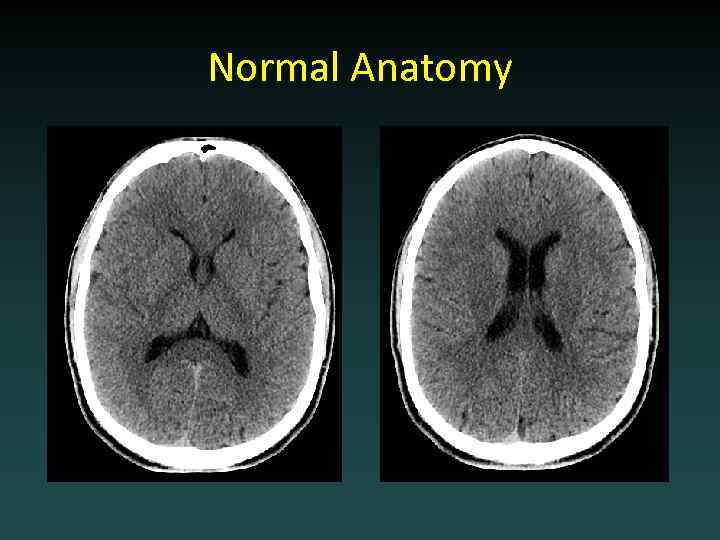

Normal Anatomy